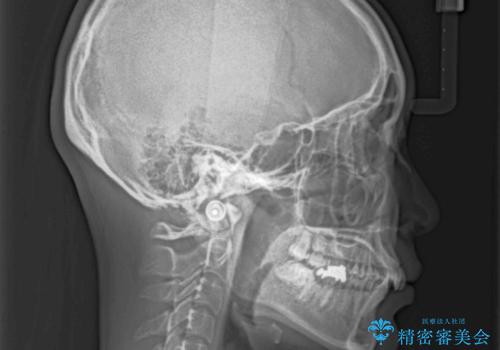

上顎歯列が、下顎に対して前方にありましたが、口元に出っ歯の印象がなかったため、親知らずを抜歯した上で、上顎歯列全体を後方に移動させることとしました。

咬合力が強いため、アンカースクリューを使用し、ワイヤー装置にて矯正治療を行うこととしました。

上顎歯列を下顎に対して4mmほど移動させる必要があったため、治療は長期化することが予想されましたが、患者様にはこちらの期待以上にゴムかけなどに協力いただき、補綴治療も含めて2年強で終えることができました。